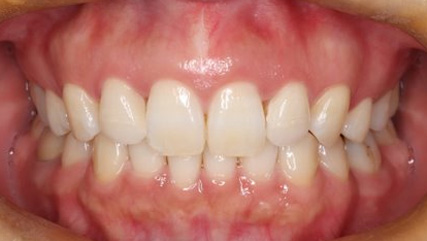

上顎前突といわれ、上顎の前歯が唇側に出ている状態を言います。

前歯が出ることで見た目の問題もありますが、口を閉じることができない、口呼吸をしてしまう、外傷などのリスクがあります。

日本人に叢生の次に多い不正咬合と言われており、自然に治ることはありません。また上の前歯が出ている事だけが気になるかもしれませんが、多くの場合、上顎の奥歯の位置に問題があることが多く、部分矯正でなく根本的な治療をした方がいい場合が殆どです。

口を閉じることができないことで、鼻呼吸でなく口呼吸をしてしまい、結果、成長期の場合顎の骨の成長を邪魔してしまうとも言われております。その他、口呼吸はアトピーなどを含むアレルギー症状の悪化、風邪を含むウイルス性の感染症にかかりやすいなどのリスクも増大してしまいます。

歯並びだけでなく全身への影響も多い為、早期の治療をおすすめ致します。

治療前

治療終了前